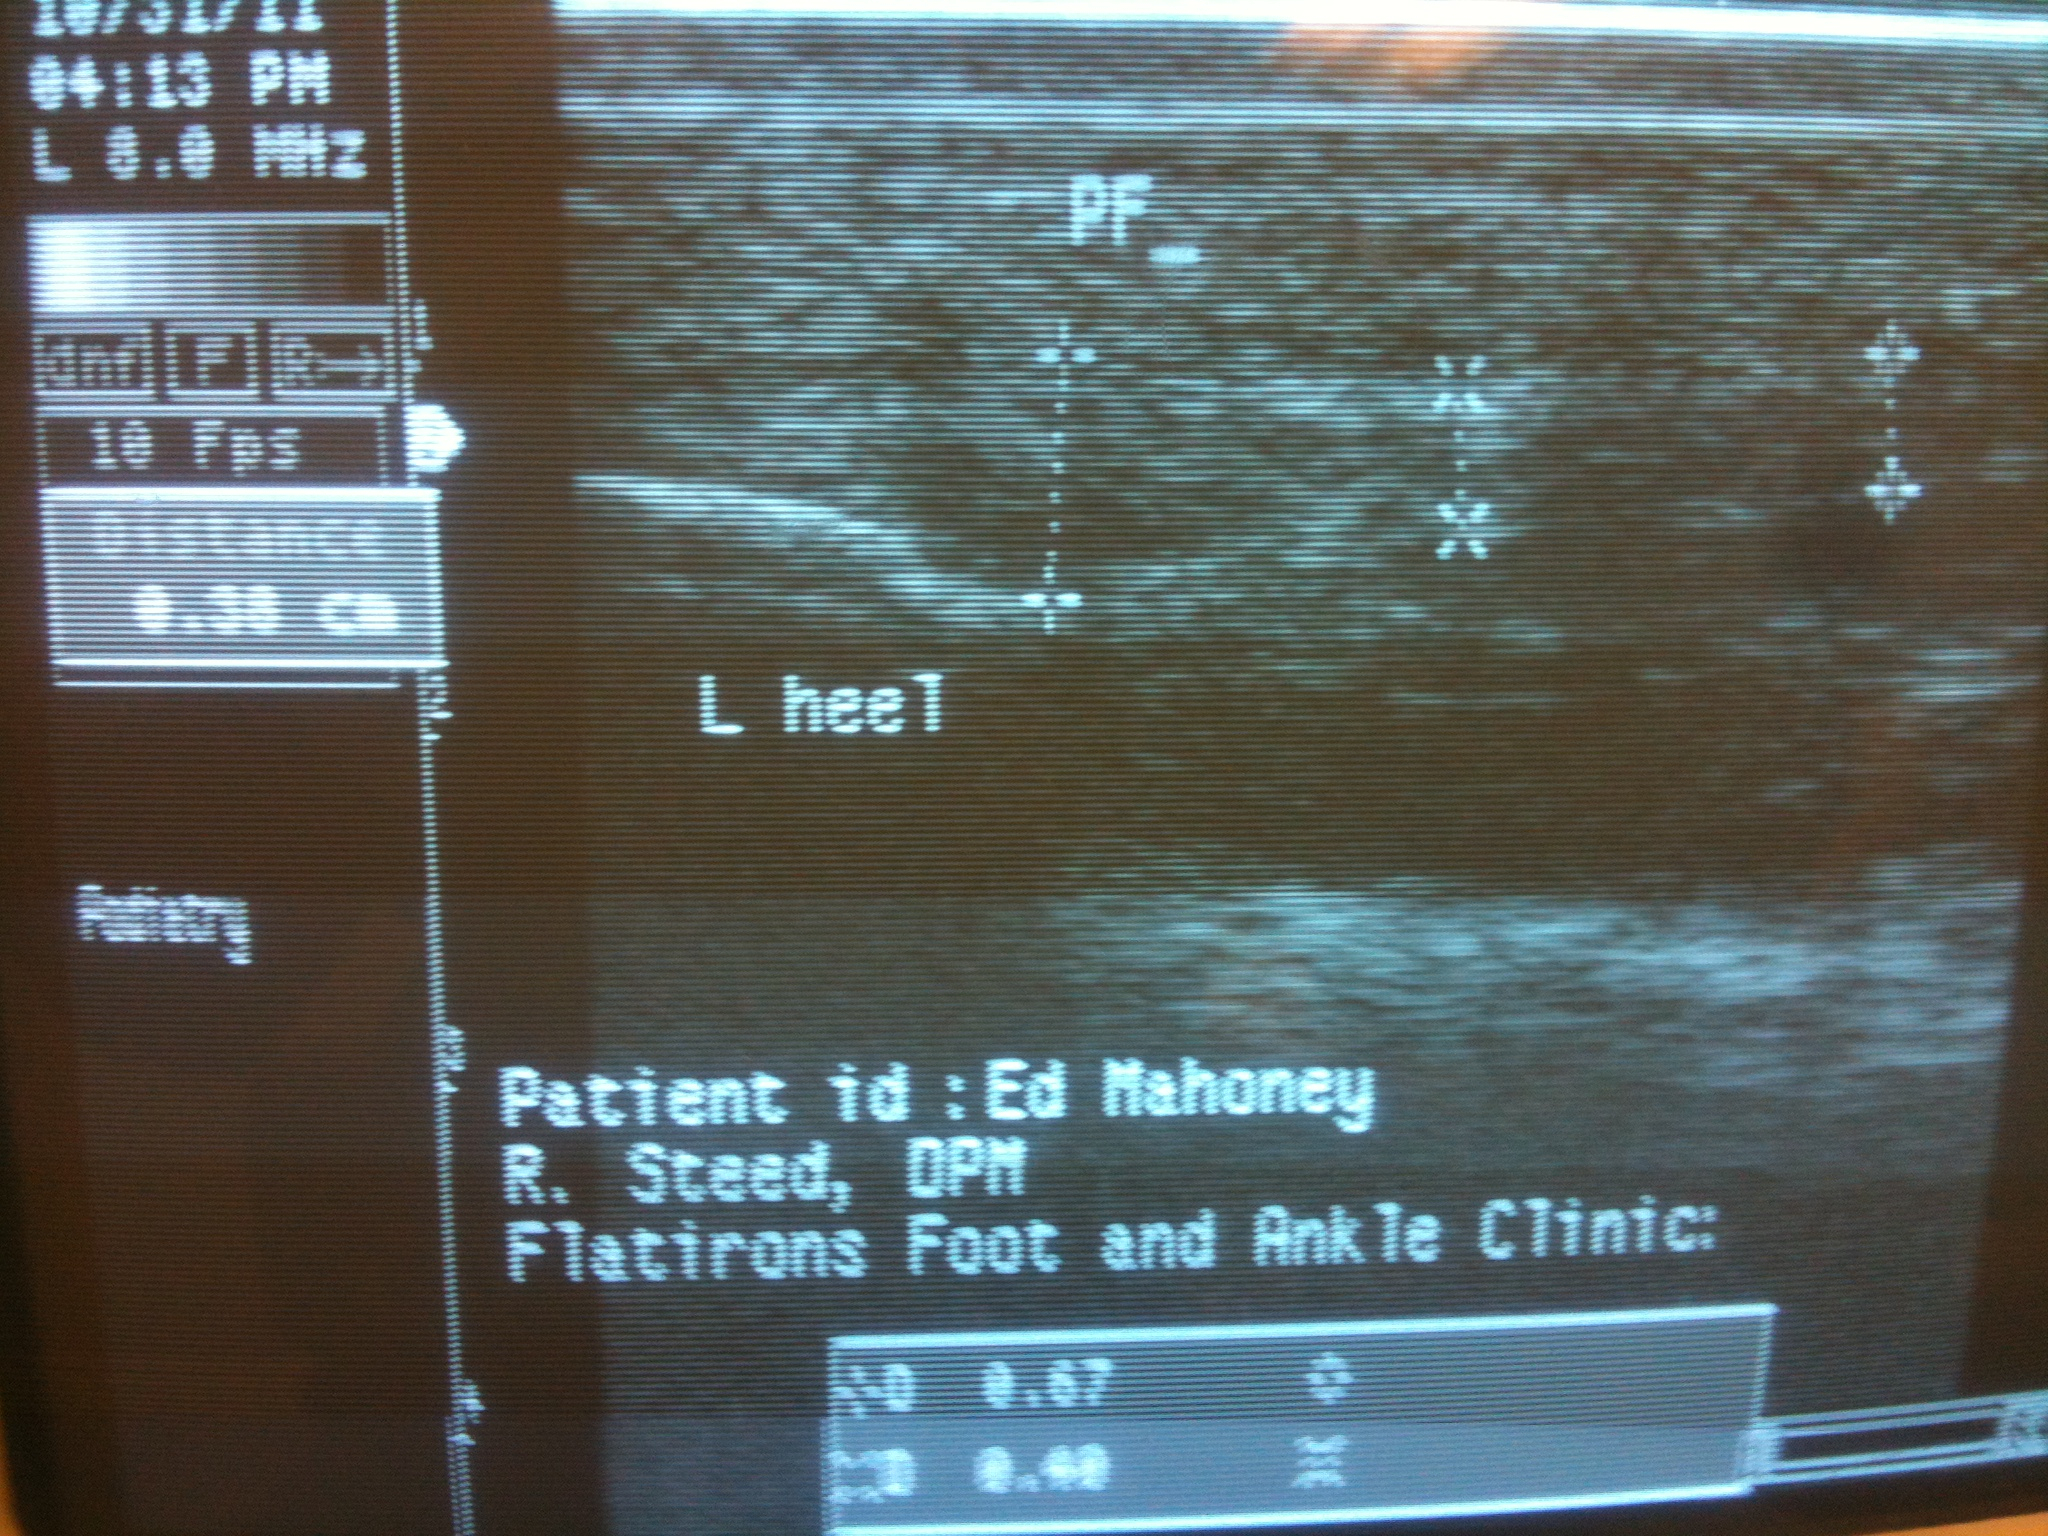

As I mentioned at the start, I’ve taken the rest of this week off from running. My knee feels totally better already; that would be stupid to let a knee injury continue. I don’t know that my plantar fasciitus will heal quite so quickly, but it should heal over time if I have the right shoes. It does feel marginally better after a few days of rest. I can tell by how sore my heel is when I wake in the morning. I’m not exactly jumping out of bed like Cameron Diaz just yet. Whatever, I’ll take a sore heel over a knee injury any day.